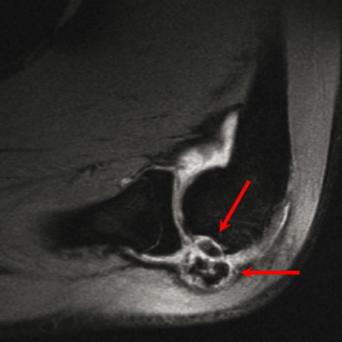

L’image

du jour

Illustration.